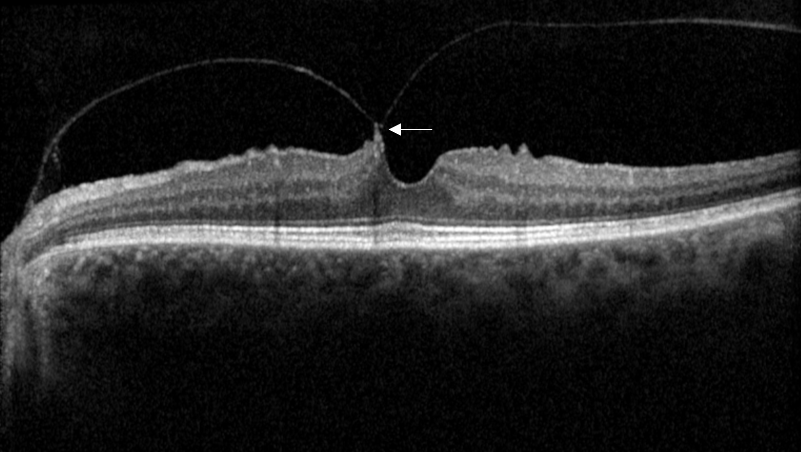

Coupe OCT, avec attache vitréo maculaire asymptomatique